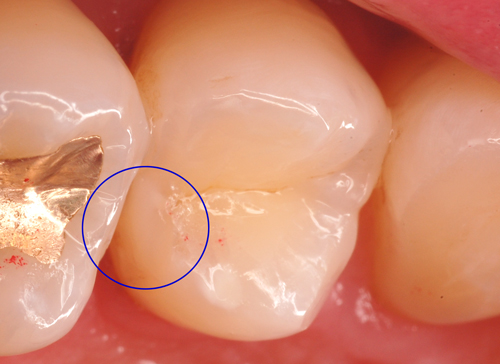

小さな虫歯なのですが実質欠損(穴)があったので治療に介入しました。セパレーターという歯と歯の間を広げる道具を使って最小限の切削で済ませています。ダイレクトボンディングが治療の選択肢にないと、隣の歯のようにインレーになってしまいます。虫歯の大きさの何十倍も大きく削る必要があります。

下の写真は治療後です。